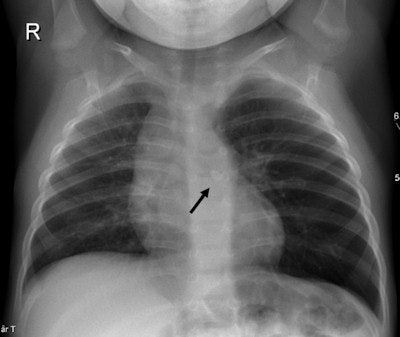

A 2-week-old baby presenting with increasing breathing difficulties and low oxygen saturation. Left: Chest x-ray shows hyperinflation in the right lung. Right: Chest CT angiography with 3D volume rendering reconstruction reveals a "pulmonary sling" where the aberrant left pulmonary artery arises from the right pulmonary artery and "slings" around the trachea and right main bronchus causing compression and stenoses.A CT scan should be ordered only when ultrasound and chest x-ray exams do not distinguish a loculated empyema from an intraparenchymal abscess or a cavitary necrosis/necrotizing pneumonia. Contrast-enhanced CT exams may be required to identify the position of drains, loculations, and parenchymal complications in patients who do not respond to treatment. Exposure to the CT radiation dose may also be warranted when imaging suppurative lung parenchymal complications because of CT's sensitivity and ability to detect and establish the extent of the complication.